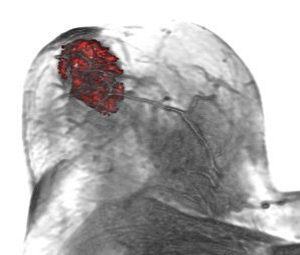

Currently X-ray mammography is the most widely used method for early detection of breast cancer. However, the use of Dynamic Contrast Enhanced MRI (DCE-MRI) has gained wider attention, since it considerably improves tumor detection and classification by analyzing the flow of contrast agent within the breast tissue. In this paper we present MammoExplorer, a CAD application that combines advanced interaction, segmentation and visualization techniques to explore Breast DCE-MRI data. Our application uses Brushing and Linking, Two-level Volume Rendering, Importance-driven Volume Rendering, and False Color Maps. In addition, we present Enhancement Scatterplots, a novel graphical representation of DCE-MRI data, novel segmentation approaches, and a new way to explore time-varying CE-MRI data.